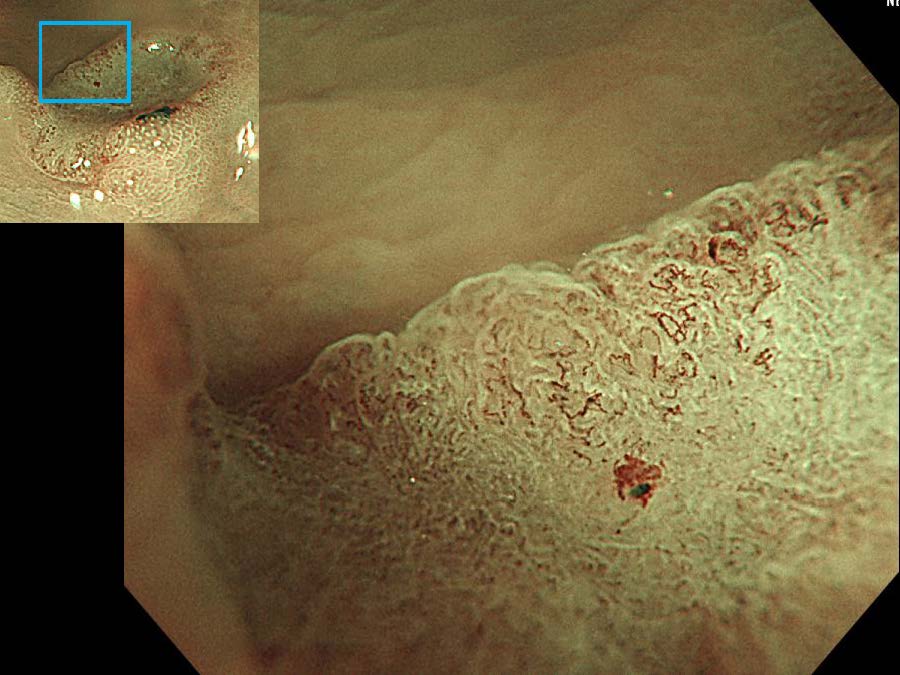

消化管Mapping~大腸~ 2021.10.27

消化管Mapping

消化管Mapping~大腸~

消化器内科

内視鏡検査・治療